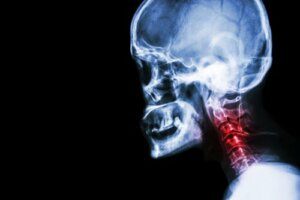

One of the causes of neck pain is cervical spondylosis. This disorder involves wear on two specific elements of the spinal column: The cartilage and bones in the neck.

According to Dr. Rubin, cervical spondylosis is a degeneration fo the hones of the neck (vertebrae) and the intervertebral disks. It exercises pressure, compressing the spinal medulla in the neck area. Therefore, it’s such a painful condition.

In general, this degeneration tends to begin rather imperceptibly around the age of 40. Therefore, it’s common in people over the age of 50 to 55 years.

It’s important to note that the intensity of symptoms doesn’t always correlate with what image diagnostics reveal. In fact, there are many patients over the age of 60 who have no symptoms. However, X-rays reveal the damage.